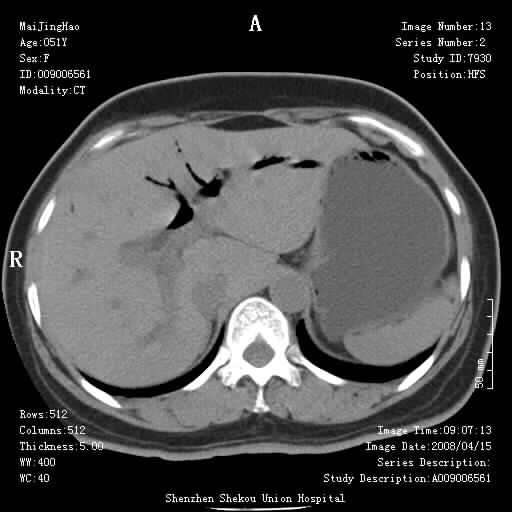

以下是引用余辉在2008-4-26 8:55:00的发言:[br]患者有结石史,此次腹痛4小时,胆总管全程扩张,应有胆总管末端梗阻,此次仍考虑胆结石症,积气不外两种原因,一种是结石下移时肠道内气体逸入,其次为产气菌感染。(倒数第三幅图像于扩张之胆总管末端似可见稍高密度影,考虑为结石影)

以下是引用yangyudong333在2008-4-26 6:17:00的发言:[br]1胆系感染,可能为金葡菌感染,2考虑有化脓性胆管炎致胆总管扩张,3胰头部增大,建议做增强

以下是引用听蝉观竹在2008-4-26 11:41:00的发言:[br]胆道手术分两种情况:[br]1、如果仅仅做胆囊切除手术,肝内胆管不会积气,只会出现胆总管代偿扩张,因为奥迪氏括约肌依然功能正常胆道与外界并不相通;[br][br]2、胆囊切除+胆总管空肠吻合手术(即roux-y式),则肝内胆管会出现积气,只是因为胆管与小肠相通,气体来源于小肠。这是临床十分常见的手术。[br][br]这个病例应该是胆囊切除+胆总管空肠吻合手术,是正常手术后表现,并不是胆道感染的表现。

以下是引用听蝉观竹在2008-4-27 10:10:00的发言:[br]关于胰头大小问题有几种测量方法和正常值:[br][br]1、直量法:横径<4cm;[br]2、胰头横径与相邻层面椎体横径的比值为二分之一,超过椎体横径就提示胰头增大;[br]3、正常组成年人肠系膜上动、静脉水平夹角正常值范围为4.9°~34.7°大于35°提示胰头增大。[br][br]上述方法只是一种具体的判断,是“量”的评估,更重要的是“质”的评估:一是观察边缘是否光滑,有无局部隆起,有无分叶;二是观察密度(增强,尤其在动脉期和门脉期)是否均匀。[br][br]所以对于胰头是否有异常不仅仅是是目测可以解决问题的,不要轻易就说“胰头增大”。还有一个问题就是测量胰头应该在增强ct上进行,这样可以避免将血管测量进去。[br][br]为什么啰嗦讲怎么多,因为我们实际工作中同样存在影像科医生和临床医生动不动就说胰头增大,说是胰头癌。大家看看是不是这种情况?[br][br] 我个人观点-----本病例的胰头不增大。[br][br][本贴已被 听蝉观竹 于 2008-4-27 10:12:41 修改过]